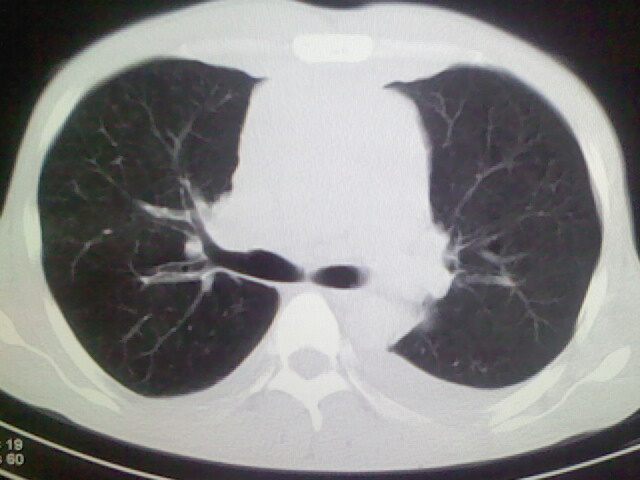

以下是引用杀毒软件在2008-9-3 6:11:00的发言:[br]侵袭性胸腺瘤------一般不侵到气管旁[br][br]考虑----纵隔淋巴瘤,心包及胸膜受累

以下是引用随光逐影在2008-9-3 7:07:00的发言:[br]1)考虑淋巴瘤可能。2)双侧胸腔积液(以左侧为甚)。3)心包积液。